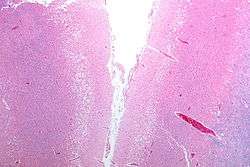

A slice of brain from the autopsy of a person who had an acute middle cerebral artery (MCA) stroke

Strokes can be classified into two major categories: ischemic and hemorrhagic.[11] Ischemic strokes are caused by interruption of the blood supply to the brain, while hemorrhagic strokes result from the rupture of a blood vessel or an abnormal vascular structure. About 87% of strokes are ischemic, the rest being hemorrhagic. Bleeding can develop inside areas of ischemia, a condition known as "hemorrhagic transformation." It is unknown how many hemorrhagic strokes actually start as ischemic strokes.[2]